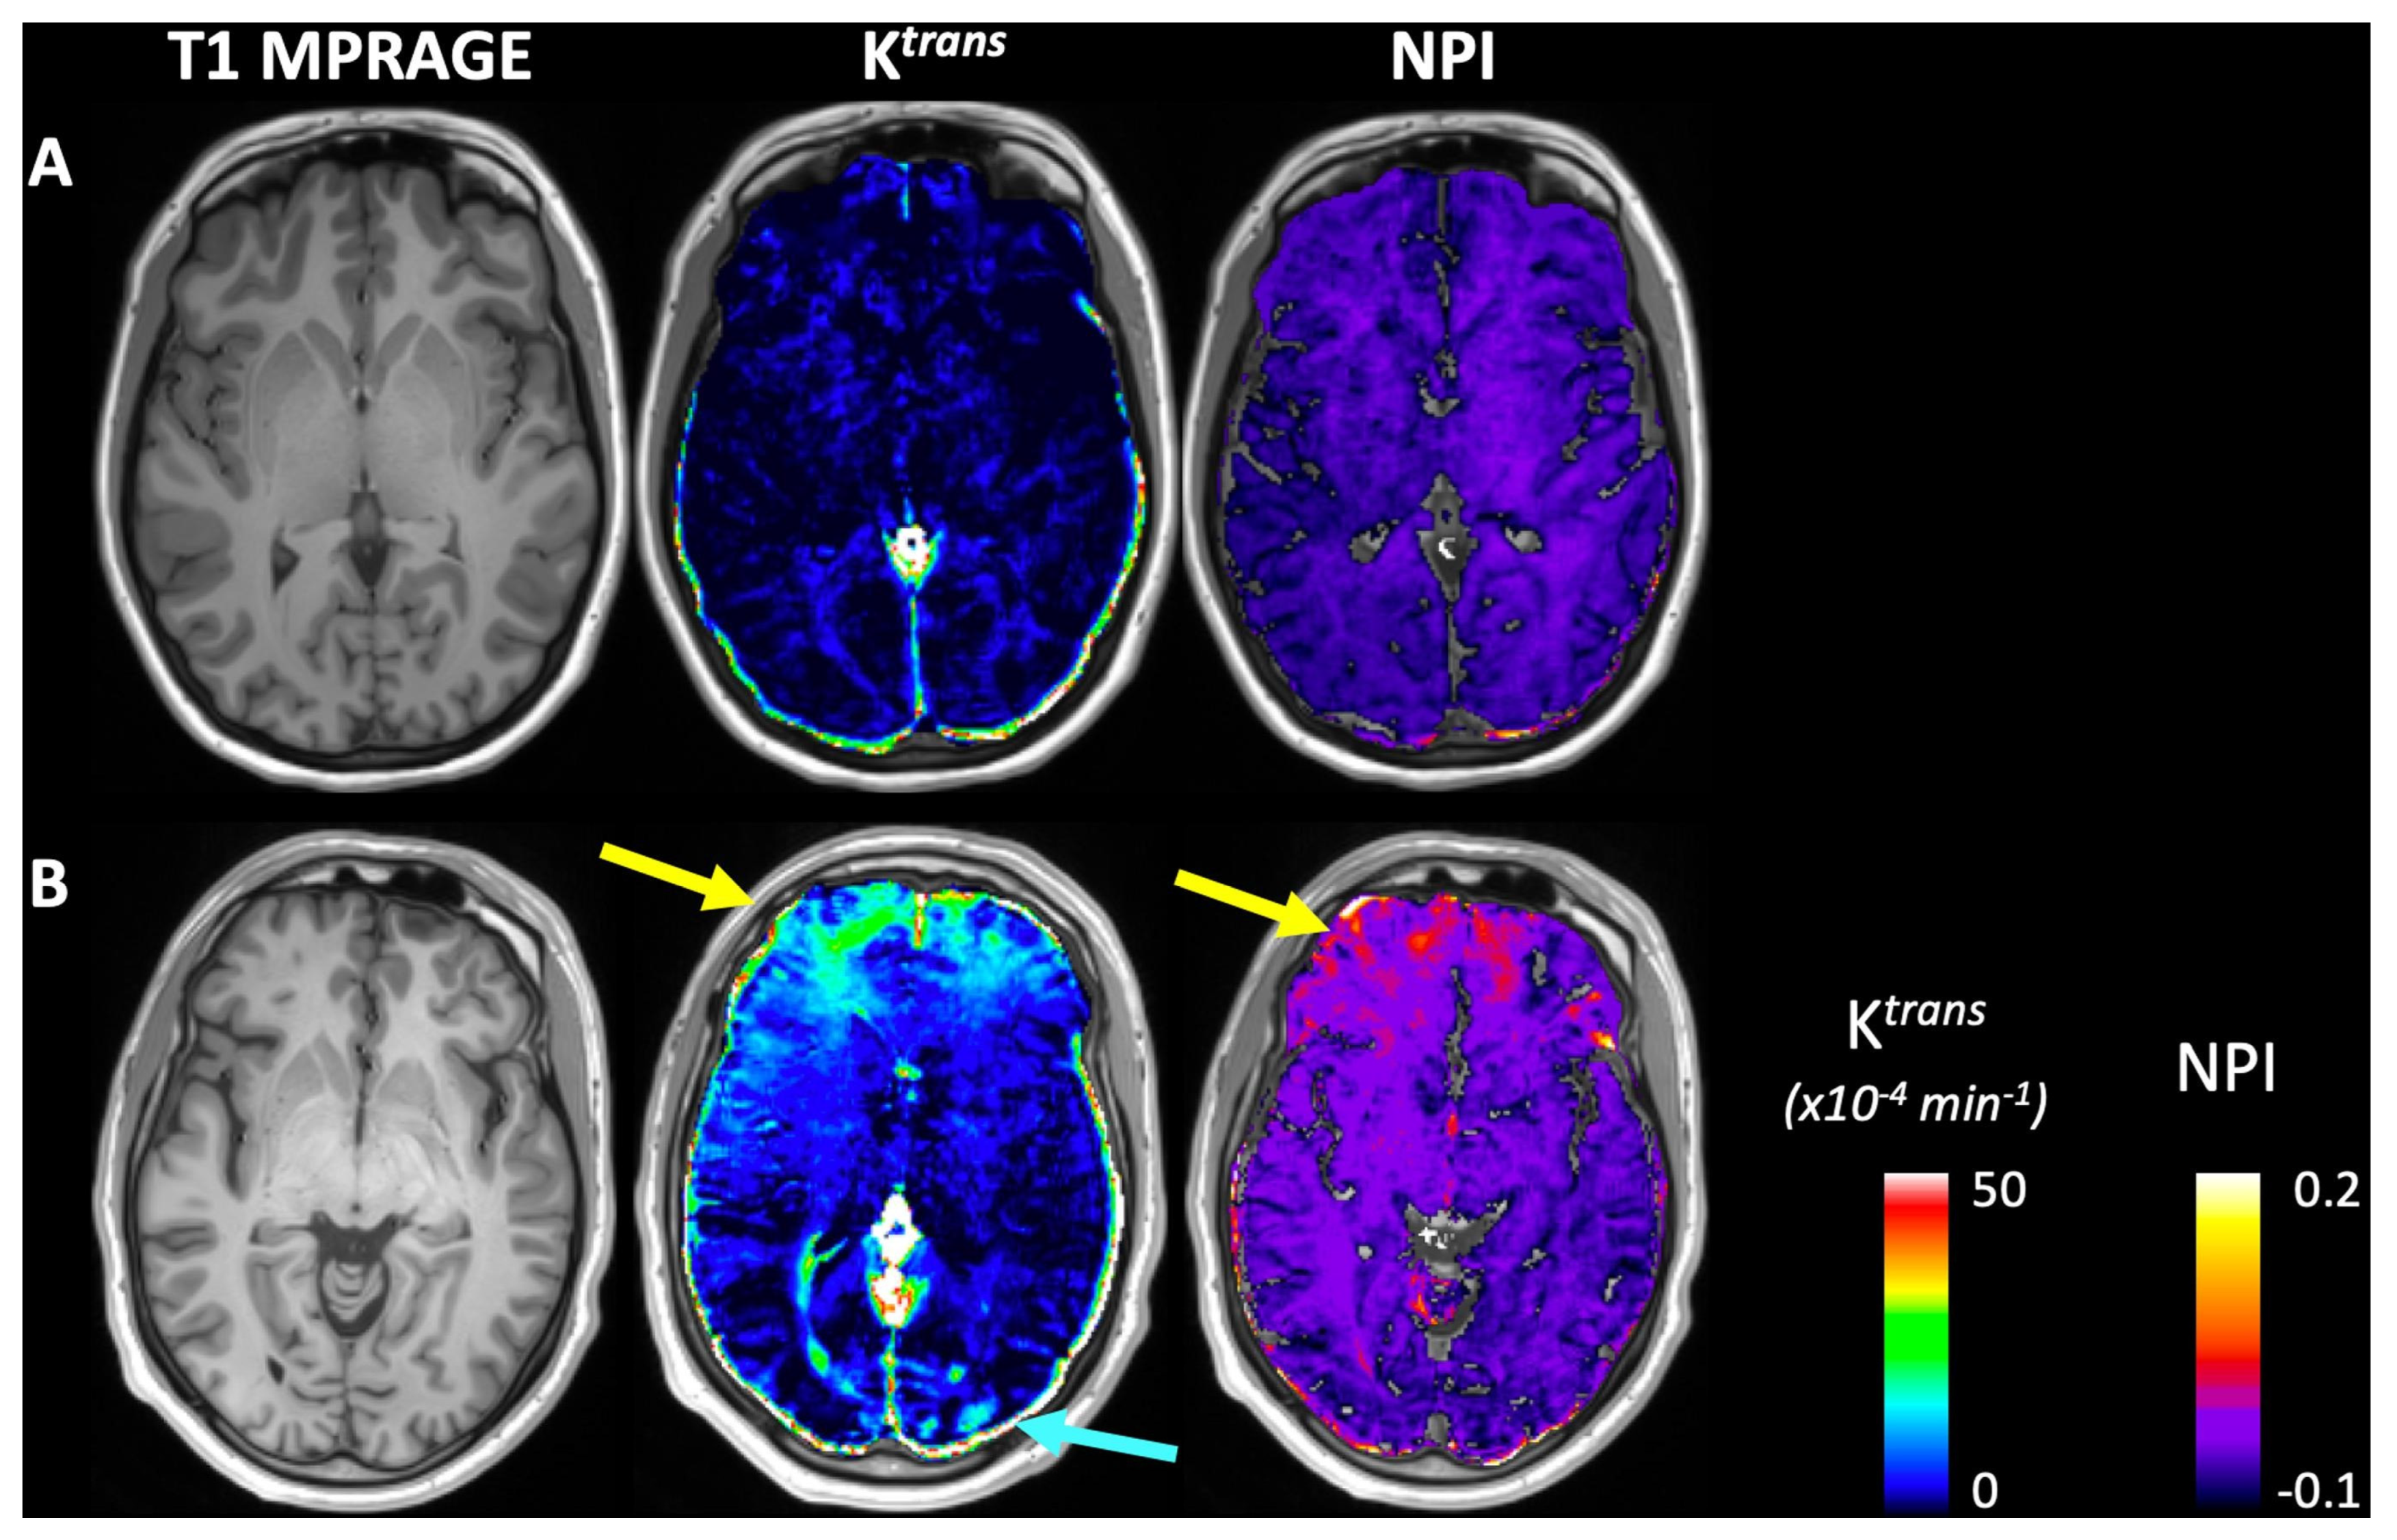

- Joseph, C.R.; Benhatzel, C.M.; Stern, L.J.; Hopper, O.M.; Lockwood, M.D. Pilot study utilizing MRI 3D TGSE PASL (arterial spin labeling) differentiating clearance rates of labeled protons in the CNS of patients with early Alzheimer disease from normal subjects. Magn. Reson. Mater. Phys. Biol. Med. 2020, 33, 559–568. [Google Scholar] [CrossRef] [PubMed]

- Joseph, C.R.; Lim, J.K.; Grohol, B.N.; Zivcevska, M.; Lencke, J.; Rich, E.D.; Arrasmith, C.J.; Dorman, I.S.; Clark, B.W.; Love, K.; et al. Identifying delay in glymphatic clearance of labeled protons post-acute head trauma utilizing 3D ASL MRI (arterial spin labeling): A pilot study. Sci. Rep. 2024, 14, 6188. [Google Scholar] [CrossRef]

- Joseph, C.R.; Kreilach, A.; Reyna, V.A.; Kepler, T.A.; Taylor, B.V.; Kang, J.; McCorkle, D.; Rider, N.L. Utilizing Reduced Labeled Proton Clearance to Identify Preclinical Alzheimer Disease with 3D ASL MRI. Case Rep. Neurol. 2023, 15, 177. [Google Scholar] [CrossRef] [PubMed]

- Voorter, P.H.M.; van Dinther, M.; Jansen, W.J.; Postma, A.A.; Staals, J.; Jansen, J.F.A.; van Oostenbrugge, R.J.; van der Thiel, M.M.; Backes, W.H. Blood–brain barrier disruption and perivascular spaces in small vessel disease and neurodegenerative diseases: A review on MRI methods and insights. J. Magn. Reson. Imaging 2024, 59, 397–411. [Google Scholar] [CrossRef] [PubMed]